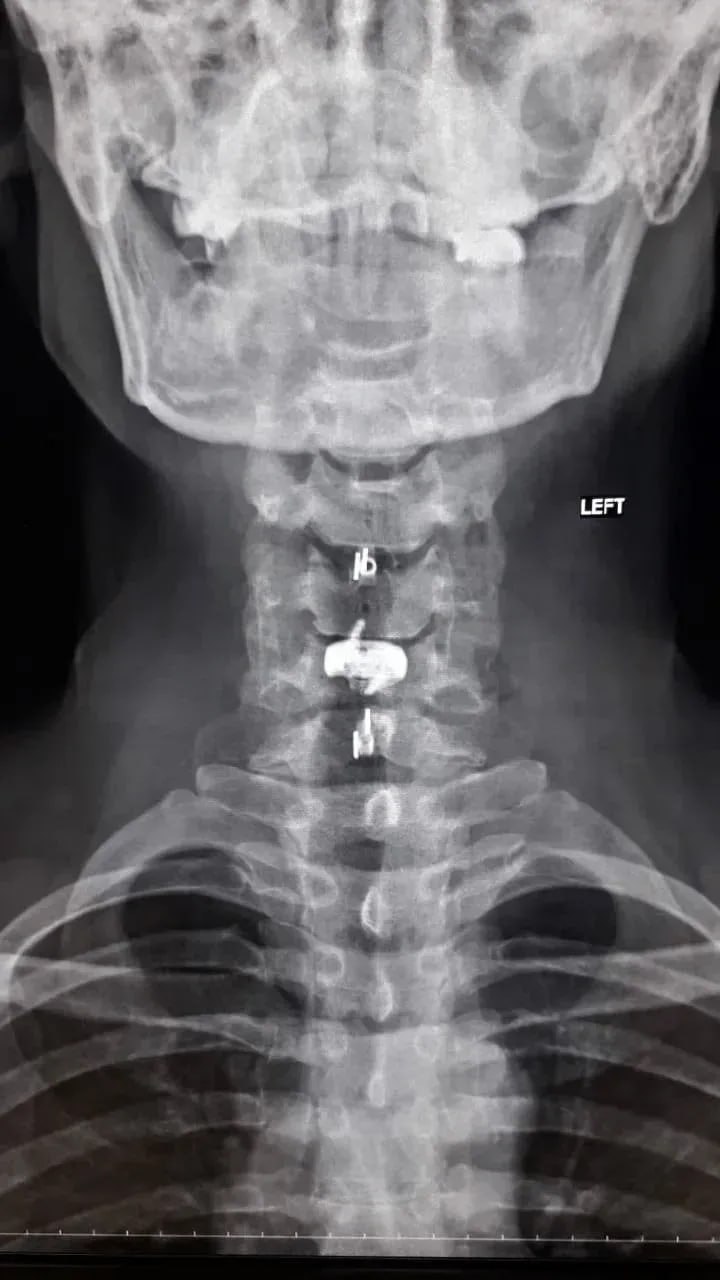

Нейрохирурги устранили стеноз позвоночного канала и стабилизировали позвоночник, одновременно укрепив его разными титановыми конструкциями. Через три часа после операции пациент уже мог вставать на ноги. Боль пошла на спад, в мышцы вернулись силы. Мужчину выписали на пятые сутки после операции. Однако его еще ждет лечение в отделении реабилитации.